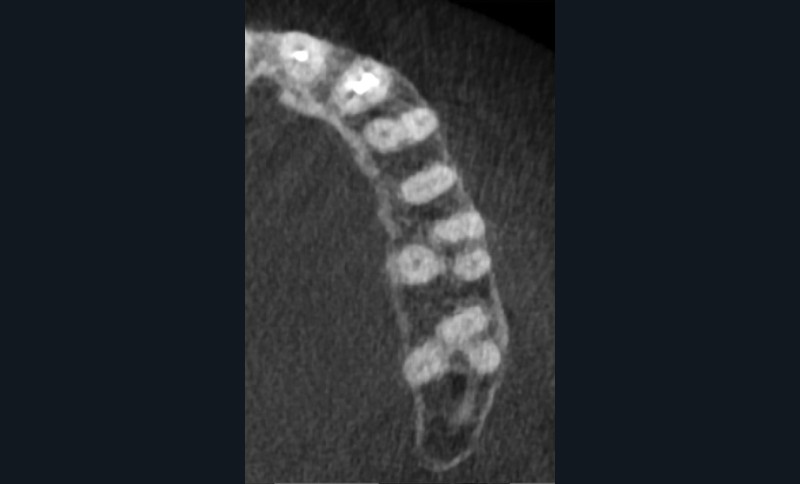

Si l’étude de Peters [18] nous montre que l’instrumentation laisse 35 % du volume canalaire non instrumenté, Ricucci et Siqueira montrent que la préparation physico-chimique n’élimine que partiellement les tissus nécrotiques à l’entrée des canaux latéraux, des isthmes et des ramifications apicales, en laissant des tissus enflammés et infectés, en association avec des lésions apicales [29] (fig. 4 et 5).

Fig. 4 – Coupe d’une racine mésiale de molaire mandibulaire avec deux canaux traités. Coupe à 3 mm de l’apex, coloration Brown et Brenn, technique modifiée par Taylor. Ces images montrent un isthme étroit avec une infection bactérienne, ce qui prouve l’importance de désinfecter et d’inclure l’isthme dans les traitements conventionnels et dans les rétropréparations apicales en chirurgie endodontique.

L’hypochlorite de sodium, communément utilisé comme irrigant pour ses propriétés antibactériennes et solvantes, se doit d’être véhiculé pour atteindre ces zones retranchées [30]. Le laser Erbium permettra d’activer localement cette solution, augmentant la densité énergétique au sein de la zone ciblée, et donc de la véhiculer. Cette solution activée par le laser se fera à un faible niveau d’énergie avec des pulses courts, afin de rester dans un mode subablatif, et de permettre la formation d’une onde de choc initiatrice d’un phénomène photo-acoustique. Ceci tout en évitant tout risque de dégradation des parois dentinaires, d’échauffement, et de dommages thermiques [31].